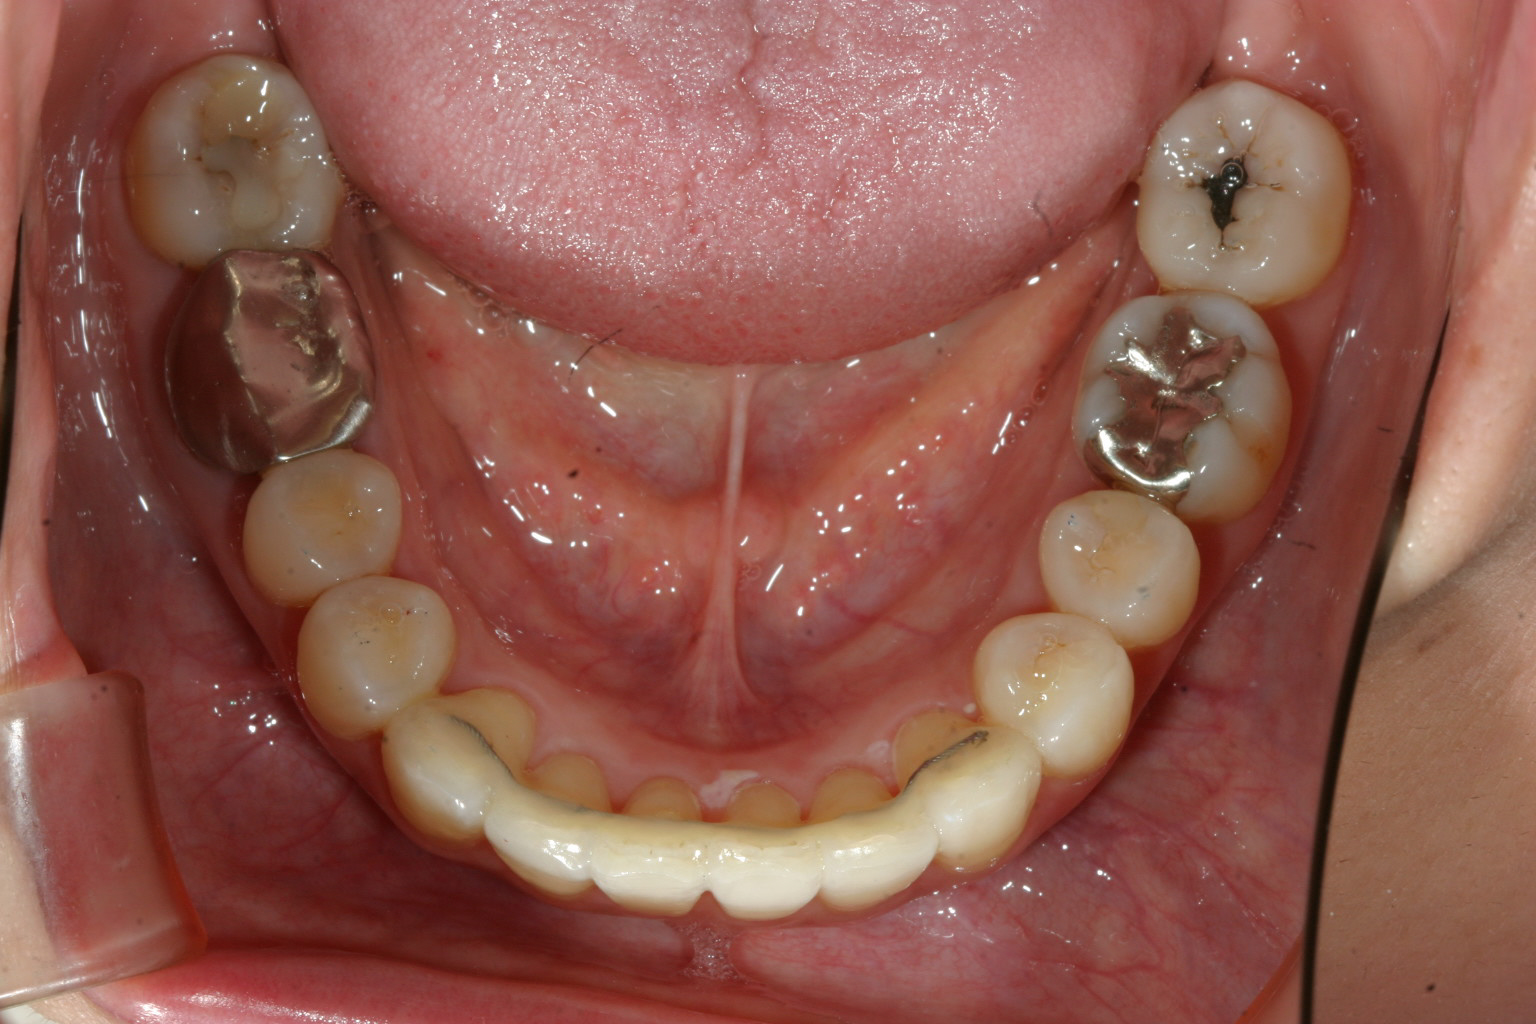

下顎の右下の2番目が少し中に入ってます。

下顎のアーチは綺麗に並びました。